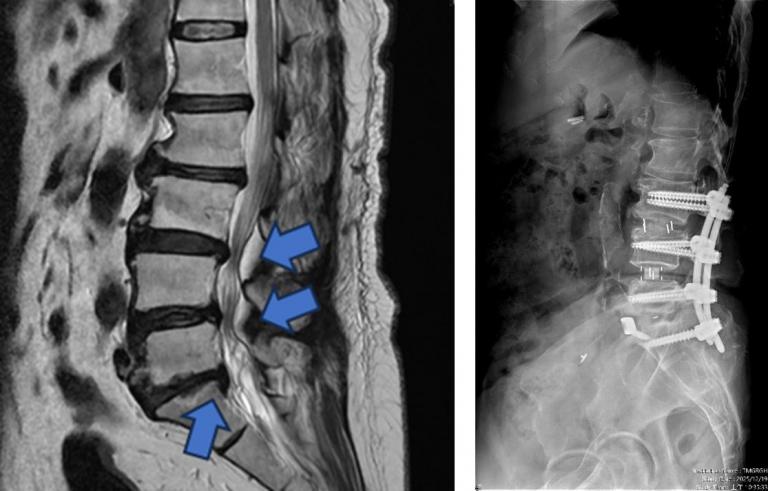

▲【手術前及手術後】手術前有脊椎滑脫不穩定及脊椎狹窄造成神經壓迫(左圖),手術後除了重建椎間高度,也將腰椎的生理曲線重建為較理想的前凸狀態(右圖)。(圖╱台中市醫提供)